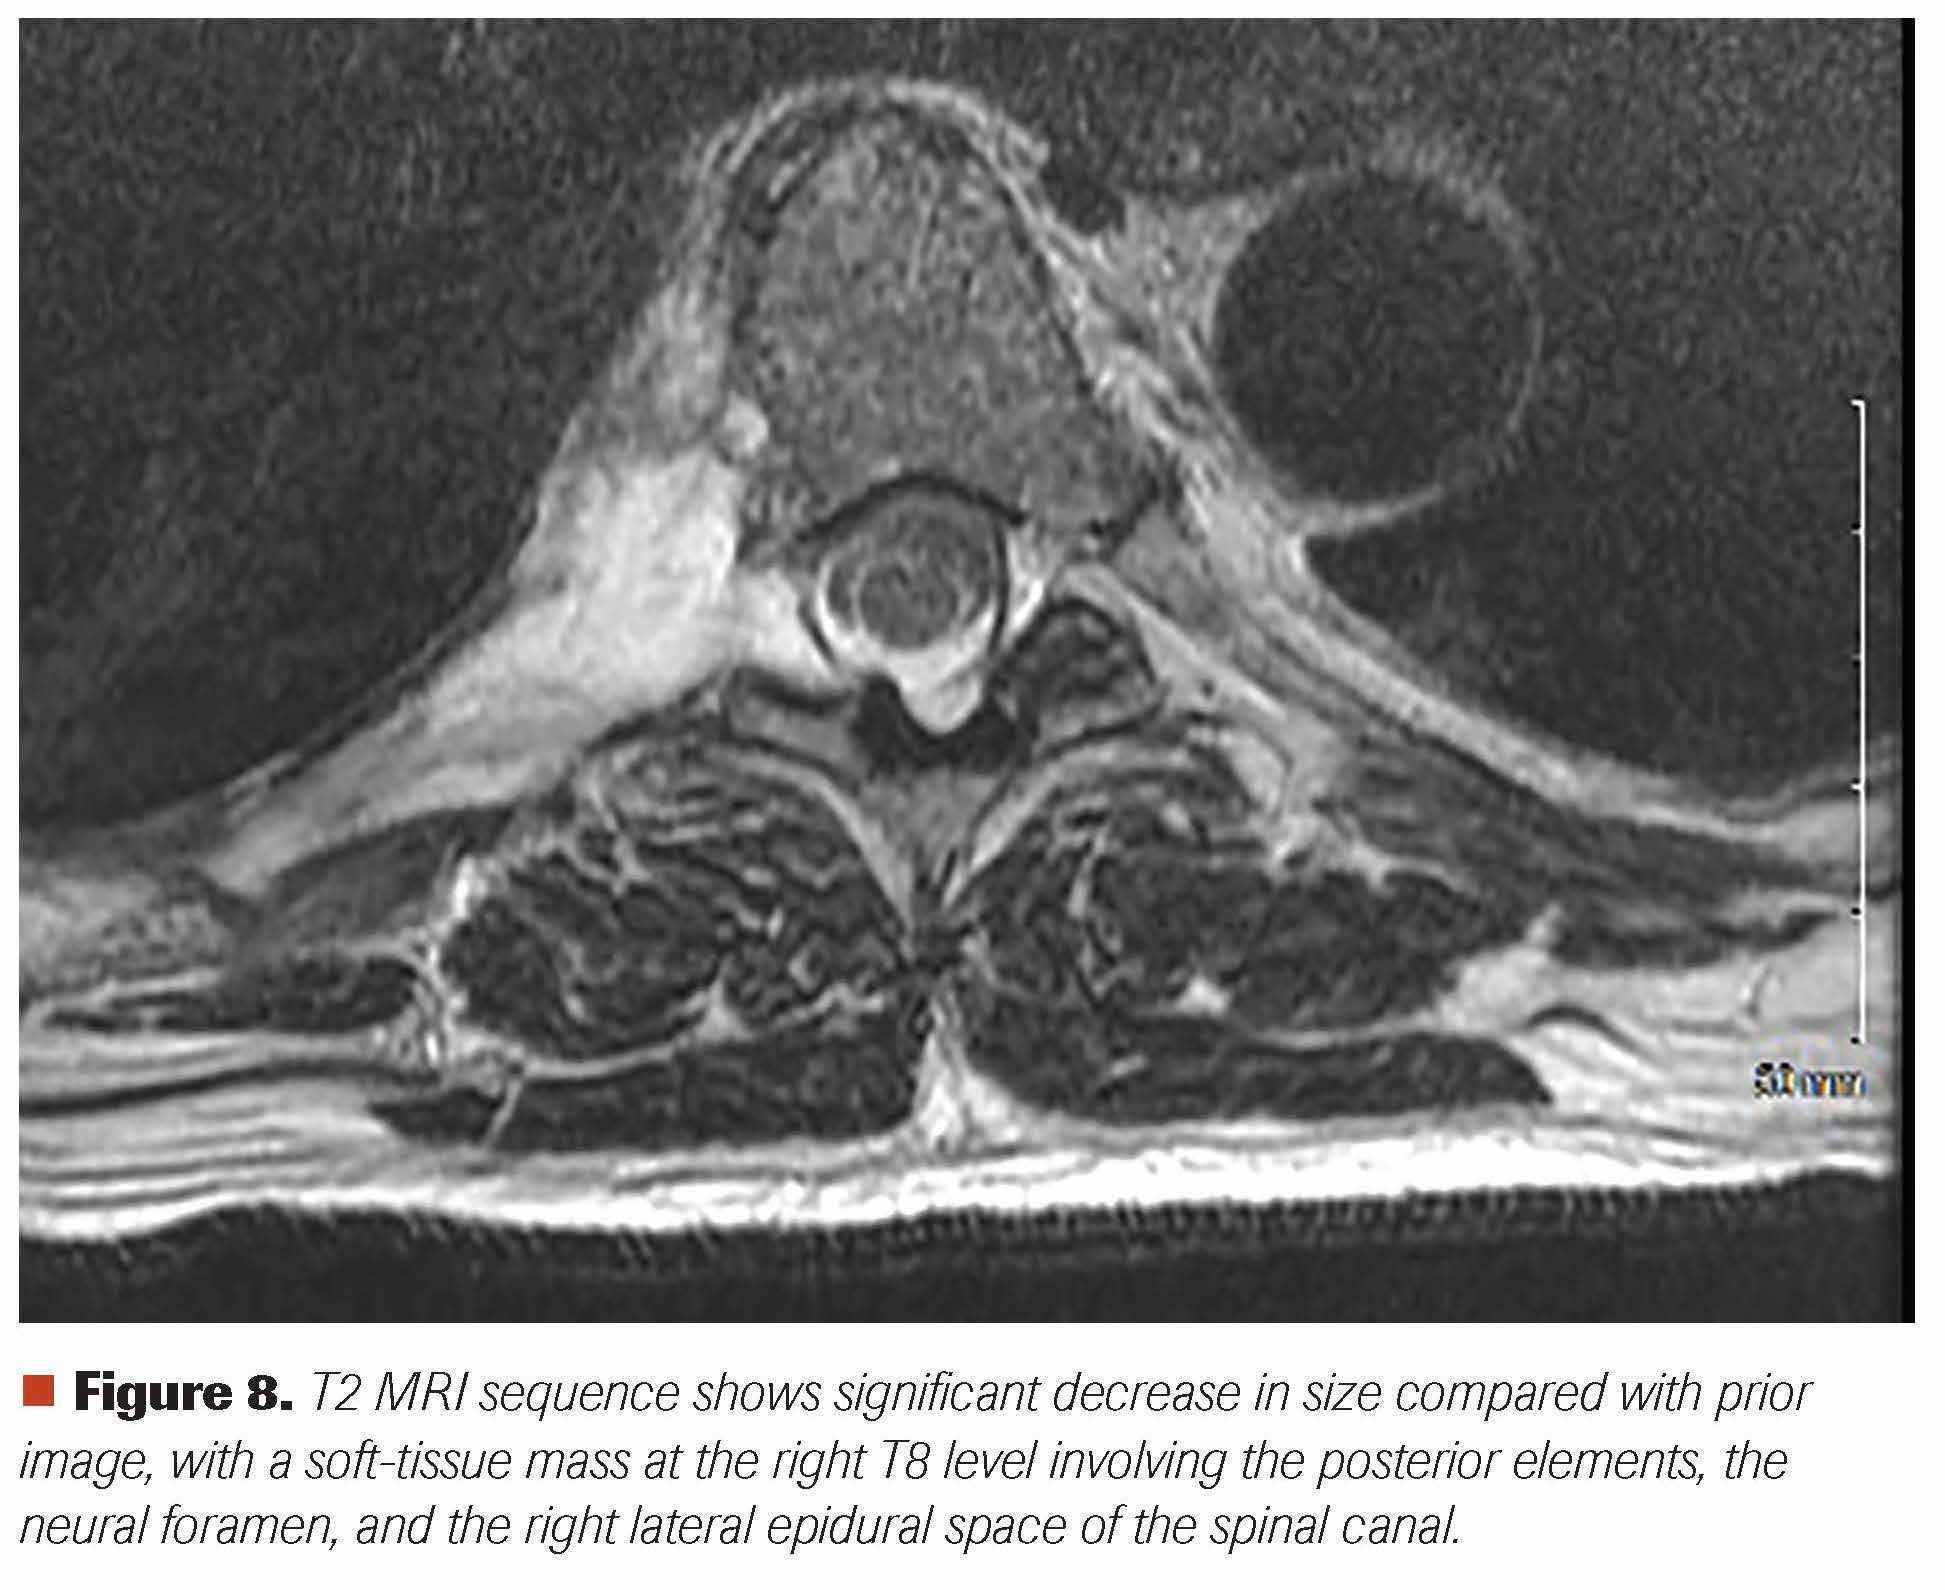

The patient was evaluated by neurosurgery, medical oncology, radiation oncology, and interventional radiology specialties in a multidisciplinary fashion. The SINS was calculated to be 4. He was started on oral dexamethasone along with EBRT to his spinal disease. He received a total of 20 Gy (5 daily fractions of 4 Gy each). Upon completion of his EBRT, he was started on a lenalidomide, bortezomib, and dexamethasone (RVD) regimen. Within the first week of his radiation treatment, he reported a 90% decrease in spinal pain. Five weeks after the start of EBRT, a repeat MRI of the spine showed a significant decrease in spinal mass (Figure 8). Following 2 cycles of RVD, a very good partial response was achieved. After the completion of 4 cycles of RVD, he will be undergoing ASCT with high-dose melphalan chemotherapy.

Figure 8. T2 MRI sequence shows significant decrease in size compared with prior image, with a soft-tissue mass at the right T8 level involving the posterior elements, the neural foramen, and the right lateral epidural space of the spinal canal.